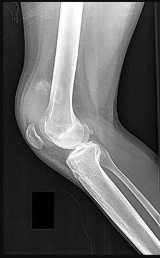

A 12-year-old obese boy presents with vague left thigh and knee pain. He is diagnosed with a Slipped Capital Femoral Epiphysis (SCFE) as seen in similar clinical scenarios.

During percutaneous in-situ fixation, unrecognized penetration of the guide wire into the hip joint occurs. What is the most likely specific complication resulting from this technical error?

Chondrolysis is a severe complication of SCFE characterized by rapid destruction of the articular cartilage. While it can occur idiopathically, its most established iatrogenic cause is unrecognized intra-articular hardware penetration. The 'approach-withdraw' fluoroscopic technique is required during pinning to assure pins are entirely intraosseous. Avascular necrosis (AVN) is usually due to damage to the epiphyseal blood supply (retinacular vessels) secondary to the initial displacement, forceful closed reduction, or posterosuperior pin placement.